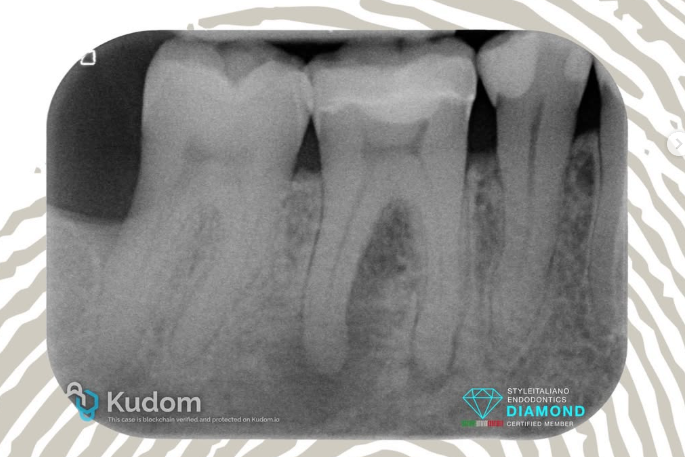

4.6: Necrosis - Big L.E.O. - Overfilling - 4 years recall

The 4.6 was treated in 2019 with an indirect restoration for the presence of a crack line.

On 2021 the patient came back to the referral complaining for a disconfort during the function.

The radiographic investigation reveals the presence of lesions in both roots of 4.6; the lesion in the distal root is bigger and it extend up to the forcation area. At the clinical examination the tooth slightly tender to percussion.

Treatment was done in 2 visits. During the first visit canals were shaped, cleaned and dressed with calcium hydroxide. After 4 weeks the canals were obturated using the Cold Hydraulic Condensation Technique, a single cone with CeraSeal bioceramic sealer, with creation of a small overfilling in the distal root.

The recall at 4 year shows the complete healing of the big lesion with no resorption of the overfilled bioceramic sealer.